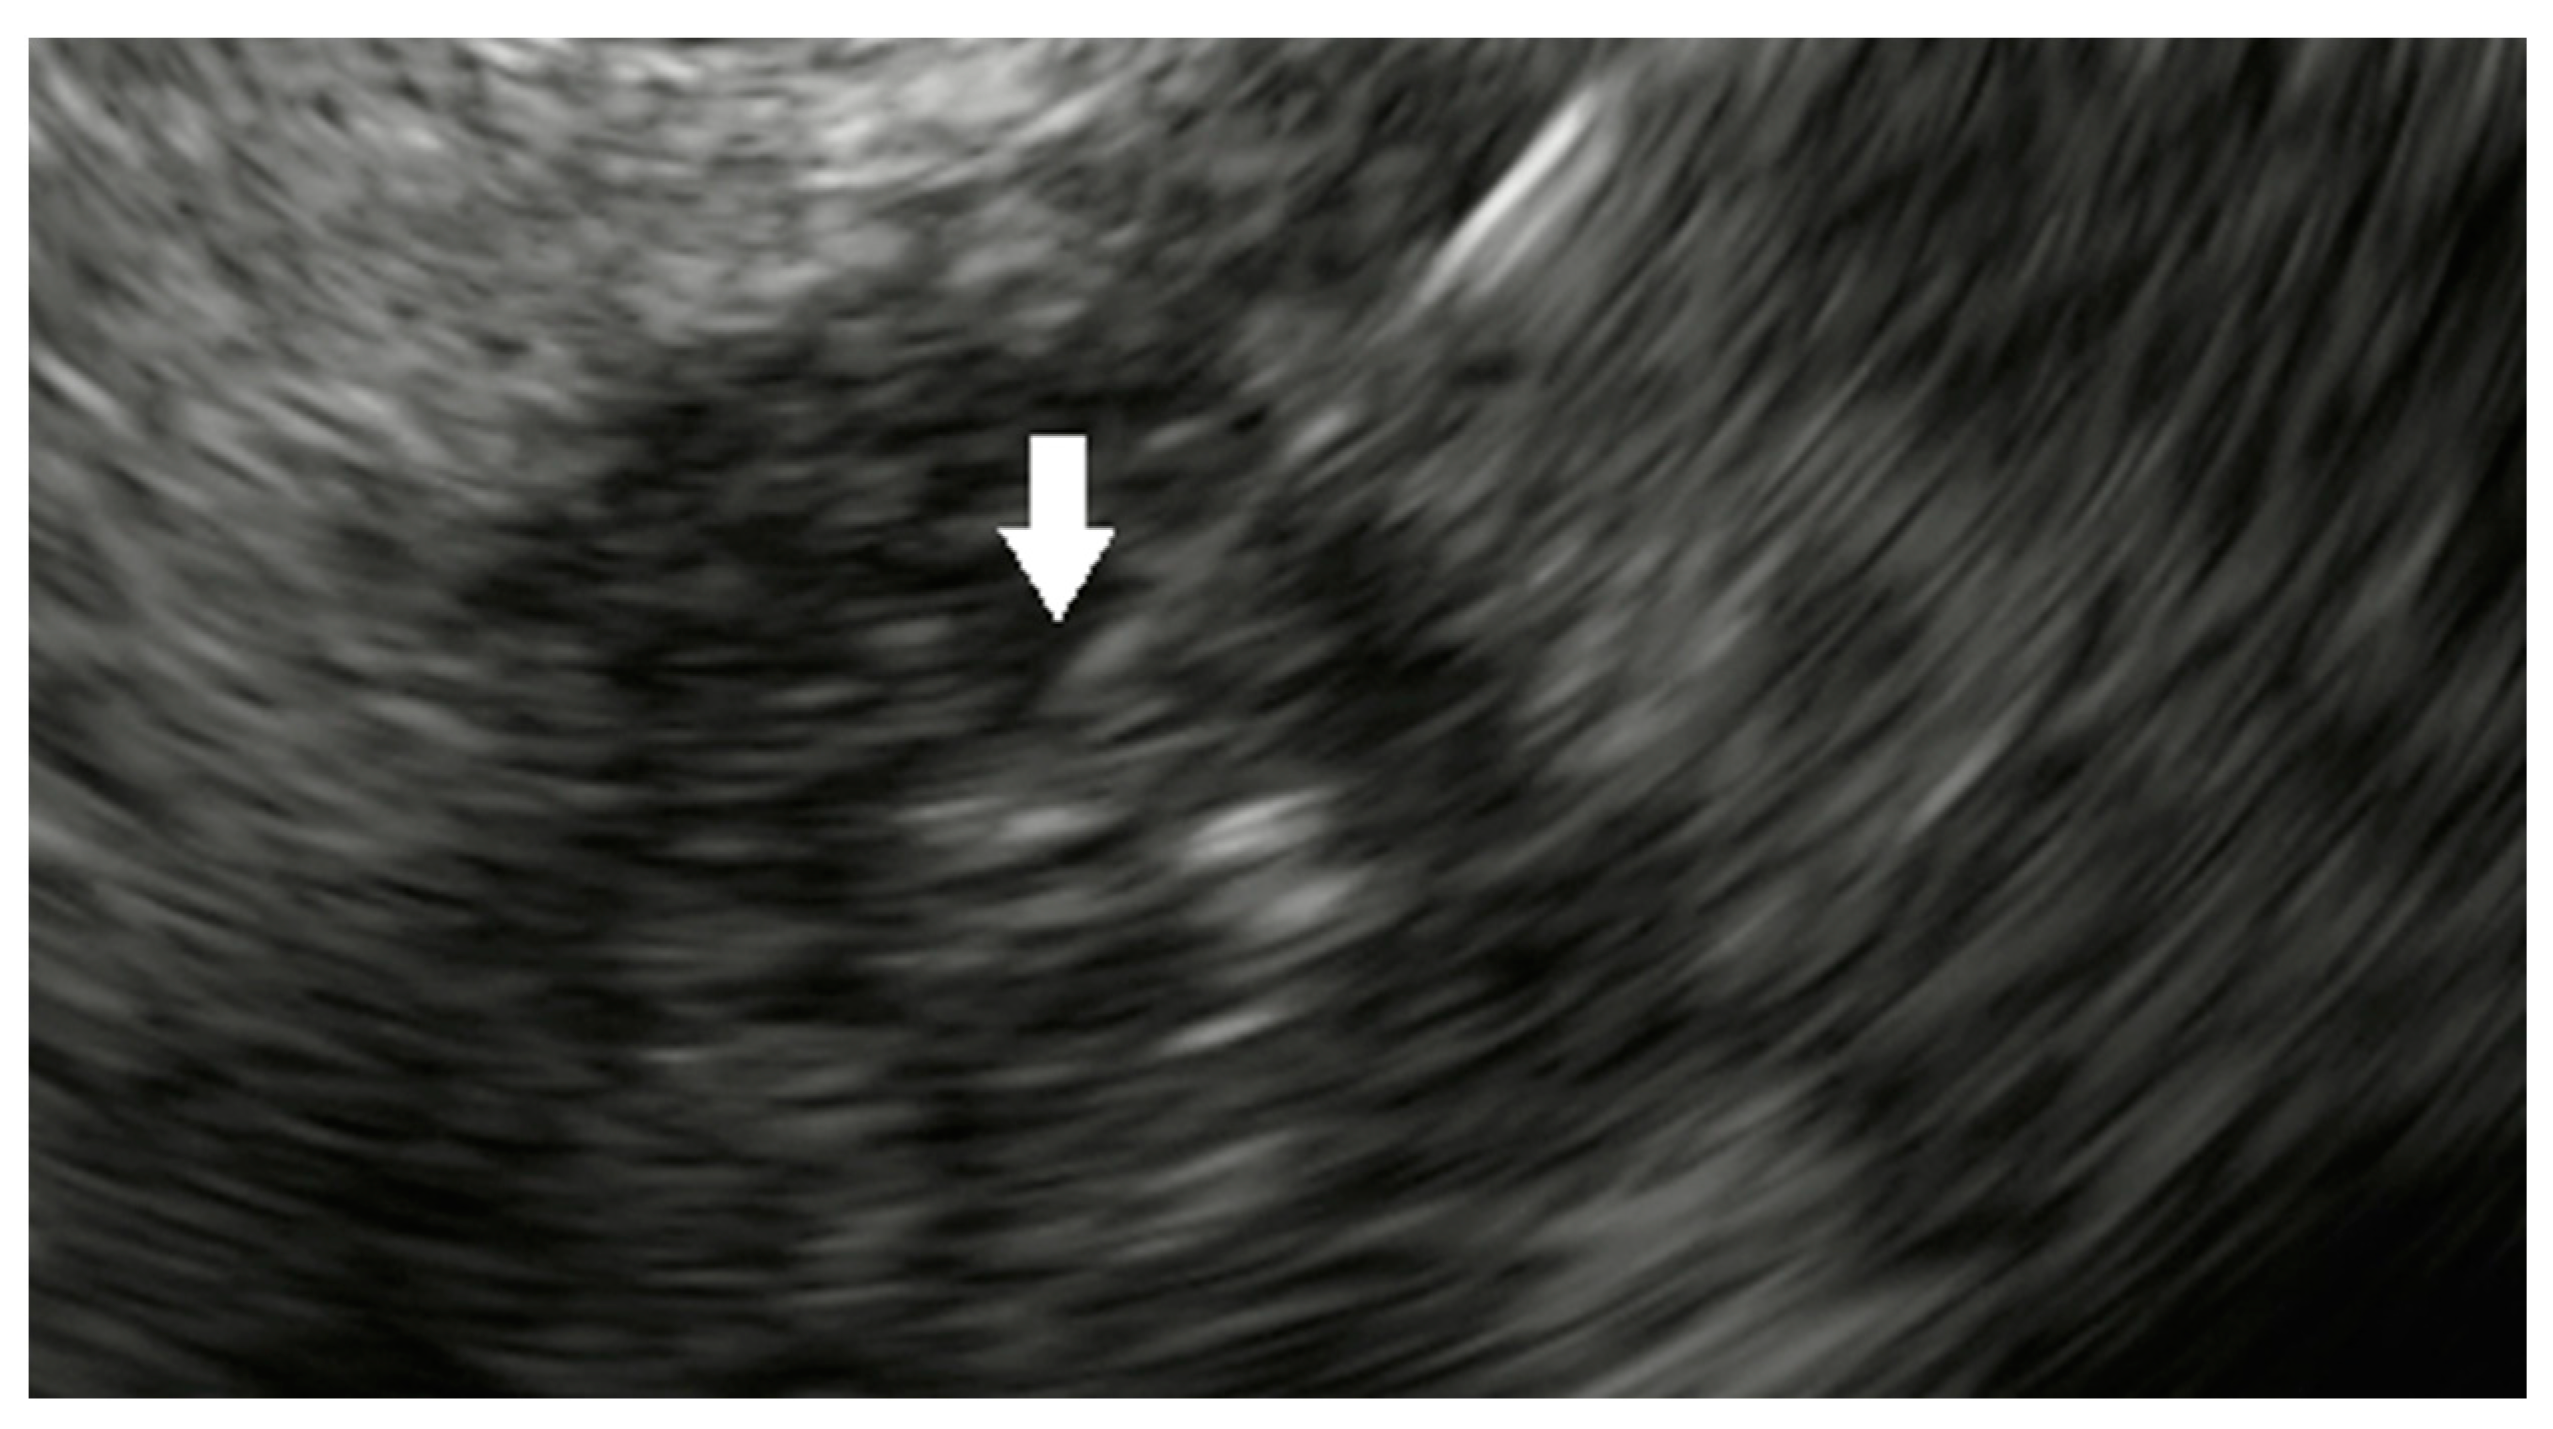

- Choi, J.-H.; Seo, D.-W.; Park, D.H.; Lee, S.K.; Kim, M.-H. Fiducial Placement for Stereotactic Body Radiation Therapy under Only Endoscopic Ultrasonography Guidance in Pancreatic and Hepatic Malignancy: Practical Feasibility and Safety. Gut Liver 2014, 8, 88–93. [Google Scholar] [CrossRef] [PubMed]

- Dávila Fajardo, R.; Lekkerkerker, S.J.; van der Horst, A.; Lens, E.; Bergman, J.J.; Fockens, P.; Bel, A.; van Hooft, J.E. EUS-guided fiducial markers placement with a 22-gauge needle for image-guided radiation therapy in pancreatic cancer. Gastrointest Endosc. 2014, 79, 851–855. [Google Scholar] [CrossRef] [PubMed]